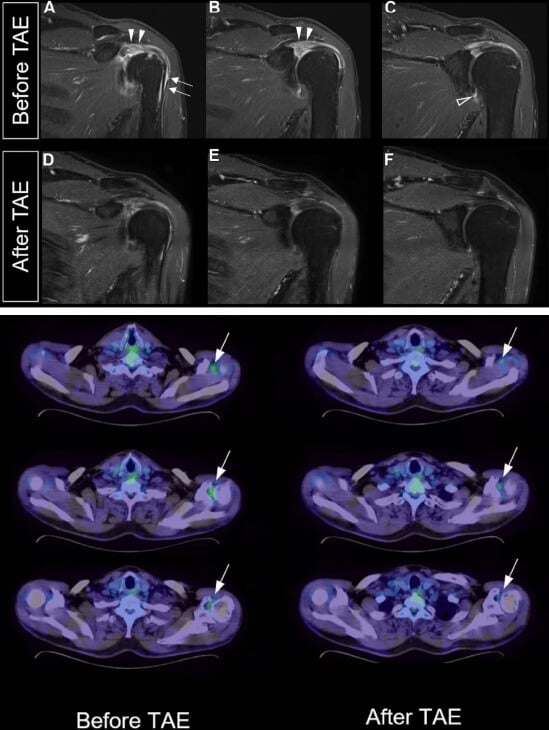

При лечении артрита плечевого сустава:

- Увеличивается объём движений, особенно при вращении наружу и отведении

- Становится легче выполнять действия с поднятыми руками, уменьшается ночная боль

- В исследовании с участием 15 пациентов с адгезивным капсулитом («замороженное плечо») после проведения артериальной эмболизации выявлена достоверная связь между снижением накопления ФДГ (показатель воспаления) и улучшением показателей по шкале боли (p = 0,039) и объема разгибания (p = 0,026)